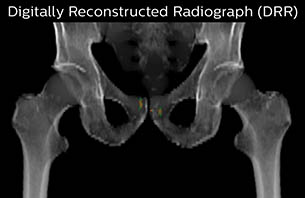

Using the mDIXON and 3D bFFE images, the RT planner marks the position of the nickel-titanium fiducial markers, and contours are transferred to the digitally reconstructed radiographs (DRRs). Reference image matching is based on these markers. “In the rare cases, where visualization of the fiducial markers fails, we do a CT to confirm their location,” Dr. Keyriläinen notes.

MR-only based planning for prostate cancer radiation therapy treatment

A 77-year-old male with prostate cancer cT3aN0M0, Gleason 8 and PSA 52 μg/L referred to androgen deprivation and radiation therapy with a prescribed dose of 50 Gy to the pelvic lymph node regions and 76 Gy to the prostate.

Turku MR-RT Digitally Reconstructed Radiograph case 6

The 3D T1W FFE mDIXON sequence provides in-phase, water and fat images in one acquisition. Target and organs-at-risk are delineated on the 3D T2W TSE images. Prostate GTV is shown in orange, PTV in purple. The 3D bFFE sequence is used by the planner to mark the position of the fiducial markers (gold anchors) and contours are transferred to the digitally reconstructed radiographs (DRRs).